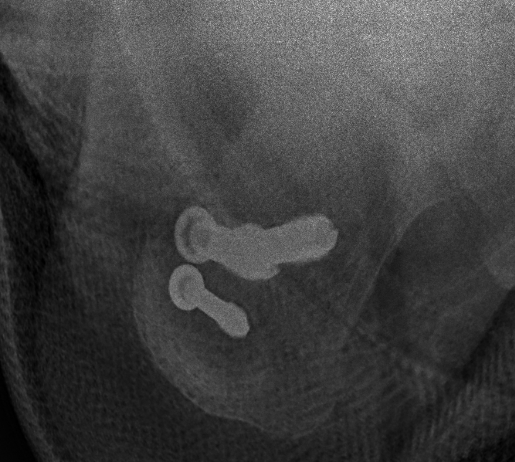

Xrays

Fixation failure with screws

Suture button fixation / Tightrope

Surgical technique suture button PDF